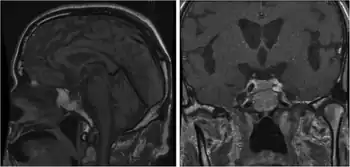

L,r)Magnetic resonance imaging after the onset of isolated adrenocorticotropic hormone deficiency